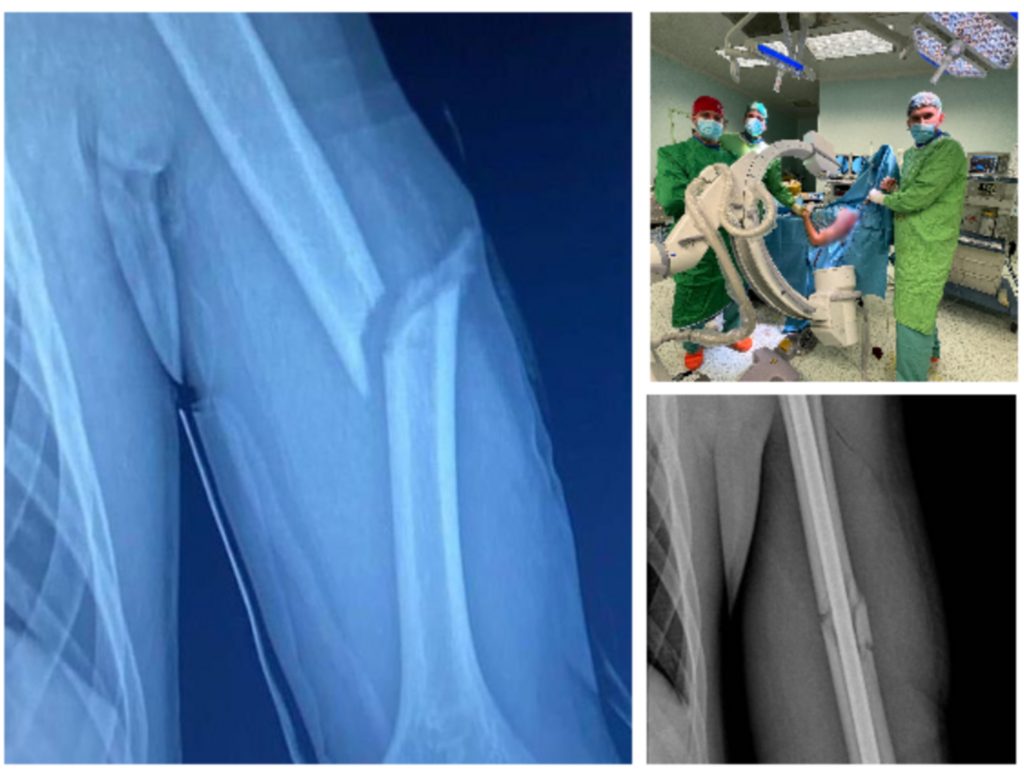

Echipa operatorie a decis să efectueze, în premieră județeană, reducerea ortopedică închisă cu osteosinteză prin tijă zăvorâtă din titan pentru un pacient pediatric. Sub control radiologic, s-a efectuat reducerea ortopedică închisă a osului fracturat, iar apoi s-a introdus o tijă de titan pentru fixarea fragmentelor osoase.

„Primul pas a presupus repunerea la loc a celor două fragmente ale osului fracturat. Cu ajutorul unor truse speciale și a ghidajului radiologic, chirurgii au introdus tija pentru a asigura poziția osului fracturat. Acest abord a presupus efectuarea de radiografii repetate în timpul intervenției pentru a se vedea unde este tija și cât de aproape este de focarul de fractură. După poziționarea acesteia pe os, următorul pas a fost montarea a 3 șuruburi pentru ancorarea tijei în humerus. Tija de titan este de calibrul canalului medular, având dimensiuni de 28 cm lungime 8 phi în diametru. Intervenția a fost una de complexitate ridicată, humerusul fiind un os foarte greu de redus. Operația a avut loc în data de 20.04.2024, a durat o oră și jumătate și a decurs bine”, a mai transmis sursa menționată mai sus.

Echipa operatorie a fost compusă din Dr. Alexandru Pîrvan, medic specialist ortopedie pediatrică și doi medici rezidenți de ortopedie-traumatologie: Dr. Barna Markus și Dr. Țapoș Cătălin. Intervenția s-a desfășurat cu pacientul intubat oro-traheal, anestezia generală fiind realizată de către Dr. Nedelcu Adina, Dr. Șuiugan Lăcrimioara, medici specialiști ATI.